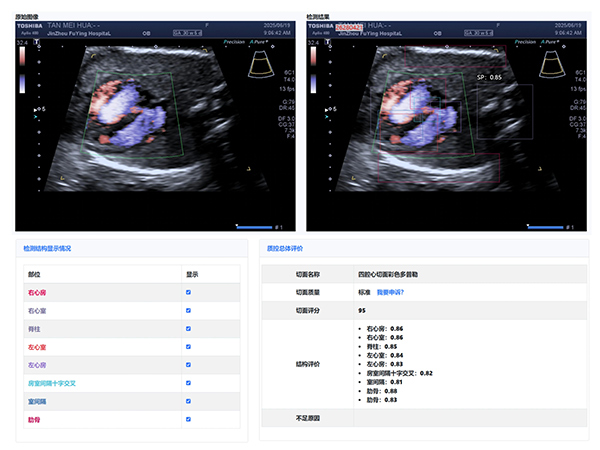

大赛汇聚了超声科全体医生,他们在产科超声领域各展所长。本次大赛引入了产前超声AI智慧云平台作为评分系统。

该平台利用先进的图像识别技术,对参赛的NT、I级、Ⅱ级、Ⅲ级产科超声图像进行精准分析与评分,确保了比赛的公正性与准确性,也体现了医院在医疗领域智能化、精准化的探索与进步。

经过激烈的角逐,年轻医生陈昱在NT产科超声图像评比中,凭借对NT精准的测量荣获第一名,展现出新生力量的专业风采;王斌医生在I级产科超声图像评比中,以精湛技术和对细节的精准把握摘得桂冠;刘芳医生的Ⅱ级产科超声图像作品,凭借清晰的图像质量和准确的诊断信息脱颖而出;Ⅲ级产科超声图像作品的评比竞争尤为激烈,李杭医生以微弱优势获得第一名。